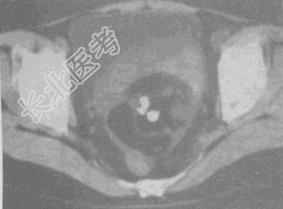

- 单项选择题女,52岁, 下腹部胀痛,B超提示盆腔占位, CT扫描如图所示,盆腔内见囊实性肿块, 其内CT值不均,从-120至300Hu不等, 最可能的诊断是

A、盆腔畸胎瘤

B、盆腔结核

C、子宫肌瘤

D、卵巢囊肿

E、卵巢黏液瘤